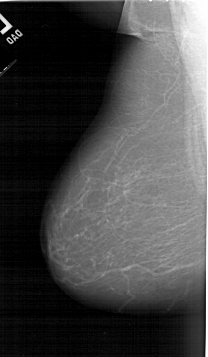

Digital Database for Screening Mammography

Volume: cancer_07 Case: A-1255-1

A_1255_1.RIGHT_MLO

ics_version 1.0

filename A-1255-1

DATE_OF_STUDY 15 10 1996

PATIENT_AGE 74

FILM_TYPE REGULAR

DENSITY 2

DATE_DIGITIZED 21 7 1998

DIGITIZER HOWTEK 43.5

LEFT_MLO LINES 6421 PIXELS_PER_LINE 3736 BITS_PER_PIXEL 12 RESOLUTION 43.5 NON_OVERLAY